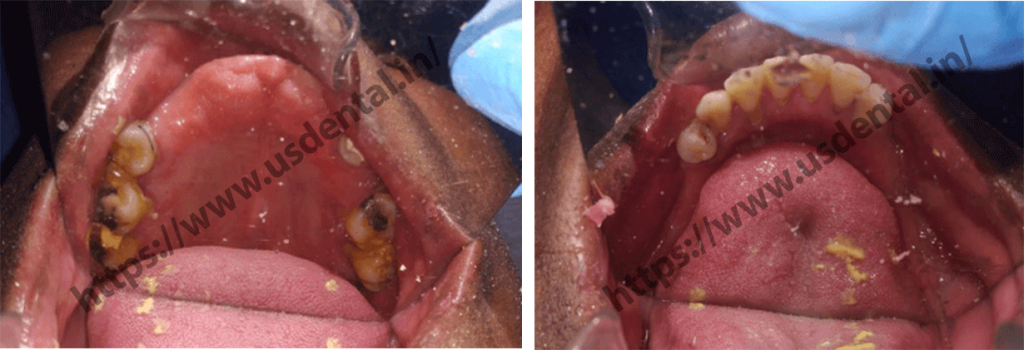

The patient visited US dental all the way from Africa with multiple missing teeth complaint. The patient had a complaint about unpleasing smile and was also unable to chew food properly. Because of the intake of unchewed food, he even started having constipation. On clinical examination, it was observed that the patient was having missing upper and lower anterior teeth.

After proper planning to mockup cast, cbct and clinical conditions, we advised patient 4 to 5 implants in the upper anterior region of the jaw and two implants on both side posterior region of the lower jaw. Implant placement was done with the help of computer guided surgery. The provisional bridge was given to the patient for three to four-month time. As advised, the patient revisited to our

dental clinic in Ahmedabad after a time period of 4 months. By that time, the patient was having lower removable dentures and an upper fixed bridge. After 4 months, the second stage of implants was done and multiunit with healing cap were placed. After tissue settled down, the final implant impression was taken for fabrication of a final prosthesis.

After proper planning to mockup cast, cbct and clinical conditions, we advised patient 4 to 5 implants in the upper anterior region of the jaw and two implants on both side posterior region of the lower jaw. Implant placement was done with the help of computer guided surgery. The provisional bridge was given to the patient for three to four-month time. As advised, the patient revisited to our dental clinic in Ahmedabad after a time period of 4 months. By that time, the patient was having lower removable dentures and an upper fixed bridge. After 4 months, the second stage of implants was done and multiunit with healing cap were placed. After tissue settled down, the final implant impression was taken for fabrication of a final prosthesis.

After proper planning to mockup cast, cbct and clinical conditions, we advised patient 4 to 5 implants in the upper anterior region of the jaw and two implants on both side posterior region of the lower jaw. Implant placement was done with the help of computer guided surgery. The provisional bridge was given to the patient for three to four-month time. As advised, the patient revisited to our dental clinic in Ahmedabad after a time period of 4 months. By that time, the patient was having lower removable dentures and an upper fixed bridge. After 4 months, the second stage of implants was done and multiunit with healing cap were placed. After tissue settled down, the final implant impression was taken for fabrication of a final prosthesis.